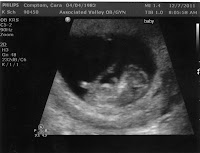

The other big November news was our announcing that we are expecting another baby! We wanted to wait until Christmas and make it a present for both your grandmas, but your mom was SO sick she didn't think she could make it through a week in Wapato without spilling the beans. So we told your Nana and P-Pa before we left and then told my parents when we back in Wapato. We told them both the same way. Your mom made you a little shirt that had a picture of a monkey on it that said "This little monkey is going to be a big sister." Both times we had to point out what the shirt said to their utter surprise and shock. Your mom thinks the letters may have been to small and I am inclined to agree. But the absolute best was your gamma Compton.